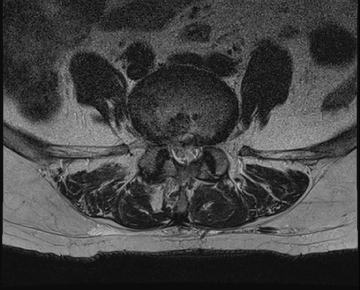

요추 협착증 수술 전·후

2022.09.01

2022.09.05

ㆍ환자 동의를 받은 자료이며, 이미지 사진은 실물과 다를 수 있습니다.

ㆍ모든 자료는 새움병원 자료입니다.